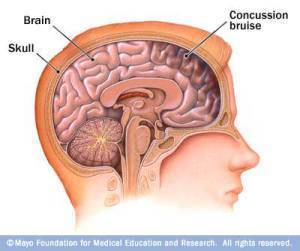

15 Points about the #Effects of #Concussions on #Meditators’ #Brains

What are the #effects of #concussions on #meditators’ #brains? Many doctors and patients now agree that #meditation helps relieve pain and stress. Therefore, meditation is recommended post-concussion for many with injured brains.

However, I haven’t found anything for my problem: my concussion makes it impossible or difficult/painful for me to meditate. What happens to those who are already long-time meditators (such as I am; 42 years), post-concussion?

6. What are the effects on various parts of the brain from a concussion? From my recent and current personal experience, I can answer that. These photos also back up my own understanding completely.

I felt pain and pressure immediately after the concussion when I automatically started to meditate which forced me to stop. Repeatedly. Over time, that pain became most apparent in three locations.

8. When we look at three brains: one uninjured, one with a concussion, and one with a severe TBI (Traumatic Brain Injury), we notice obvious differences, particularly in these areas mentioned, above:

image from http://www.vitamindwiki.com

To orient you: top of photos = forehead/frontal areas of brain. Look at the differences in these three scans in that area, particularly. Startling, huh?

9. How does a concussed brain show up on an MRI?

image from http://www.ninds.nih.gov

I could be wrong, here, but I think these scans are oriented in opposite ways from those in #8. Top = back/neck, or the occipital lobe area. Look, therefore, at the bottoms of these scans to see how the frontal areas are affected.

Remember, though: most concussion injuries and symptoms do not show up on MRIs, CAT scans or X-rays, even when taken on the same day as the injury, much less those taken weeks or months later. Functional MRIs and PET scans are slightly better, but many effects are just not all that easy to visualize with the technology currently available.

10. What other signs of impact (concussion) on a brain can we see?

image from http://www.webdicine.com

For best understanding, contrast the picture in upper left with the one in the lower right. That’s my brain. Yuck.

12. Pay particular attention to the “frontal bruise” on this concussed brain (similar to what I experienced on April 6 when I hit the wall with my nose/face and broke my nose/got concussed):

image from kerlanjobeblog.com

Don’t you just have to say “ouch!” after seeing this frontal bruising? Empathy is easier when you can see it all in front of you.